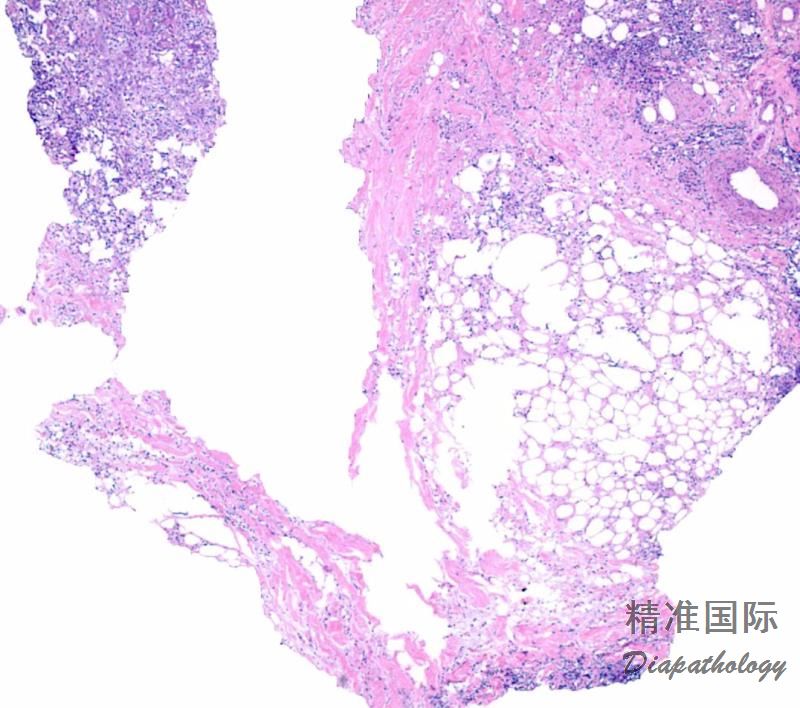

Lupus Panniculitis

好发于躯干,和上下肢的近端。亚洲人中, 以面部和头皮多见。 发生于 1-3% 的红斑狼疮病人。~ 30% 的狼疮性脂膜炎病人有圆盘性红斑狼疮。~ 10-15% 有系统性红斑狼疮。女性多于男性。 以中年病人多见, 偶见儿童。发病时间不定, 多早于,也可同时或晚于红斑狼疮。半数的病人没有红斑狼疮或其他自身免疫疾病。 因此,定义为红斑狼疮的一个类型。